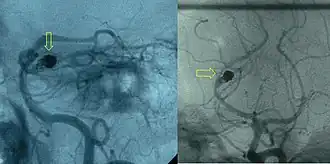

Post-embolization arteriogram showing coiled aneurysm (indicated by yellow arrows) of the posterior cerebral artery with a residual aneurysmal sac

First developed by Sadek Hilal in 1968, embolization is a minimally invasive surgical technique.[8] The purpose is to prevent blood flow to an area of the body, which can effectively shrink a tumor or block an aneurysm.